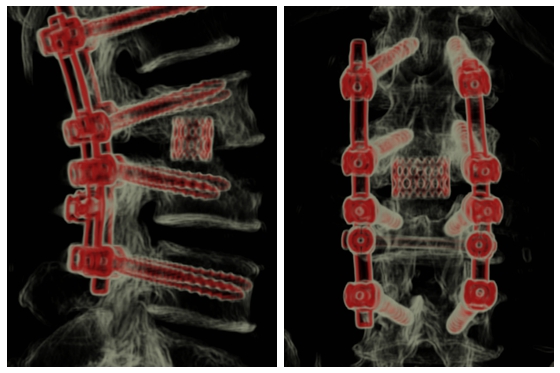

近日,中南大学湘雅医院骨科常德病区成功为一名罹患腰椎结核合并细菌混合性感染的患者实施腰椎后路感染病灶清除椎弓根螺钉固定钛笼植骨融合手术。该手术的顺利完成,标志着我院在脊...

1月21日,中南大学湘雅医院骨科常德病区成功为强直性脊柱炎患者完成高难度颈椎骨折手术。近日,患者已康复出院。 手术前后对比图 据了解,1月18日,患有强直性脊柱炎的...